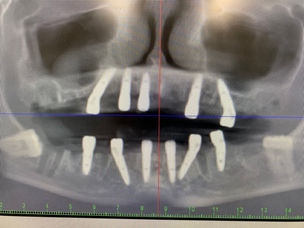

Clinical Case: 8 GDT Dental Implants Oral Surgery

The patient, a 72 year old woman, reported to the clinic with excessive tooth movement. the targeted teeth were extracted and milled